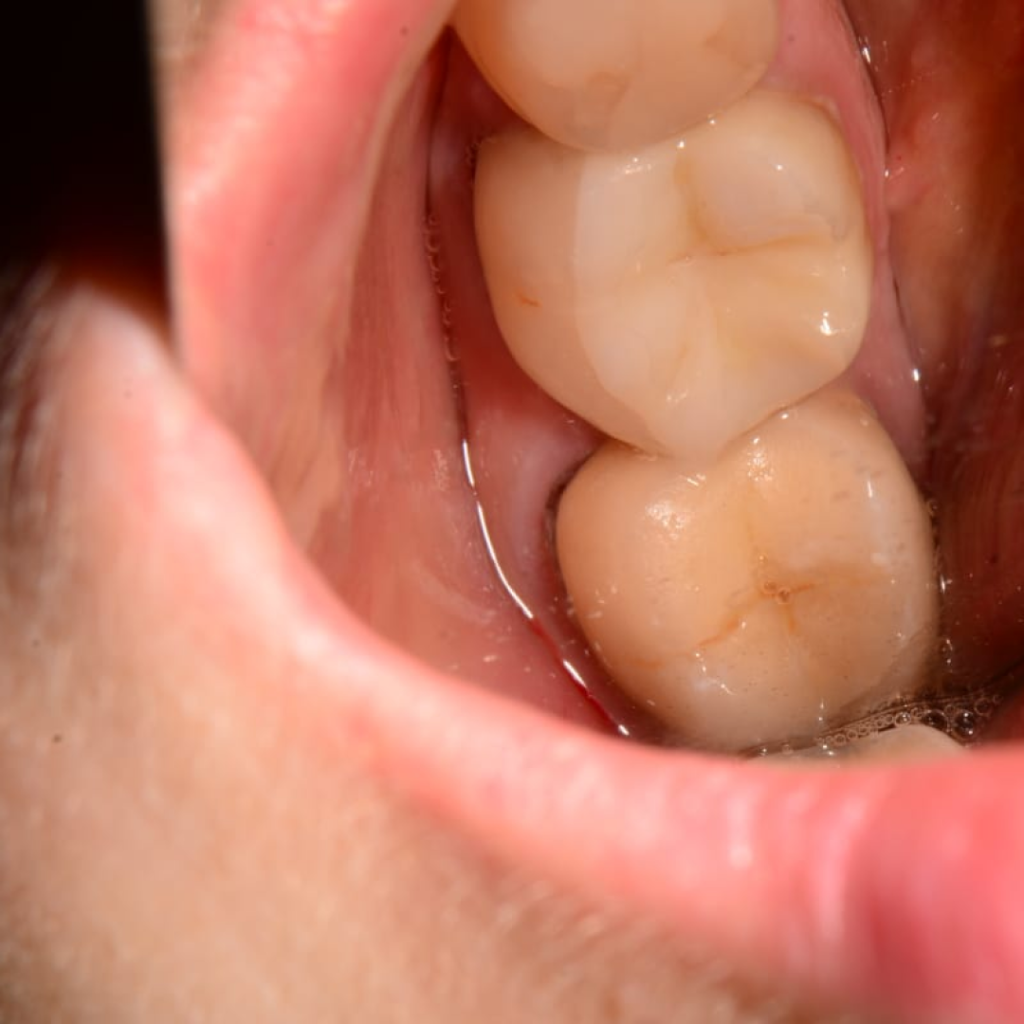

Пациентке по терапевтическим показаниям были удалены зубы 37 и 47.

Особенности анатомии зубов после удаления составили:

- сросшиеся медиальный и дистальный корень

- отсутствие межкорневой перегородки

- диаметр лунок более 11 мм